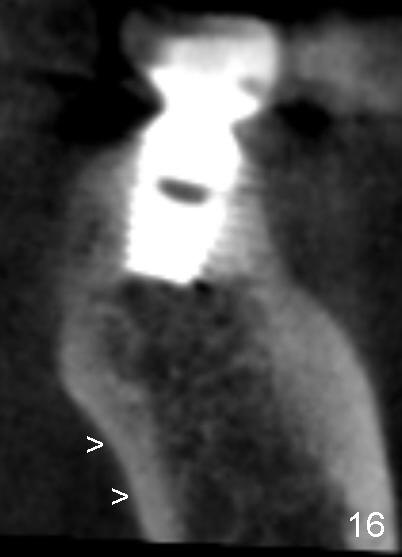

In addition, it is important to control the depth of the osteotomy. For freshly healed socket and immediately post-extraction socket, it should be safe to place a 11 mm long bone-level (Fig.15,16) or 14 mm gingival level (Fig.13,18) implant or less. For the same length, it appears safer to use a tapered implant (Fig.9,13,18) than cylindrical one (Fig.15,16).